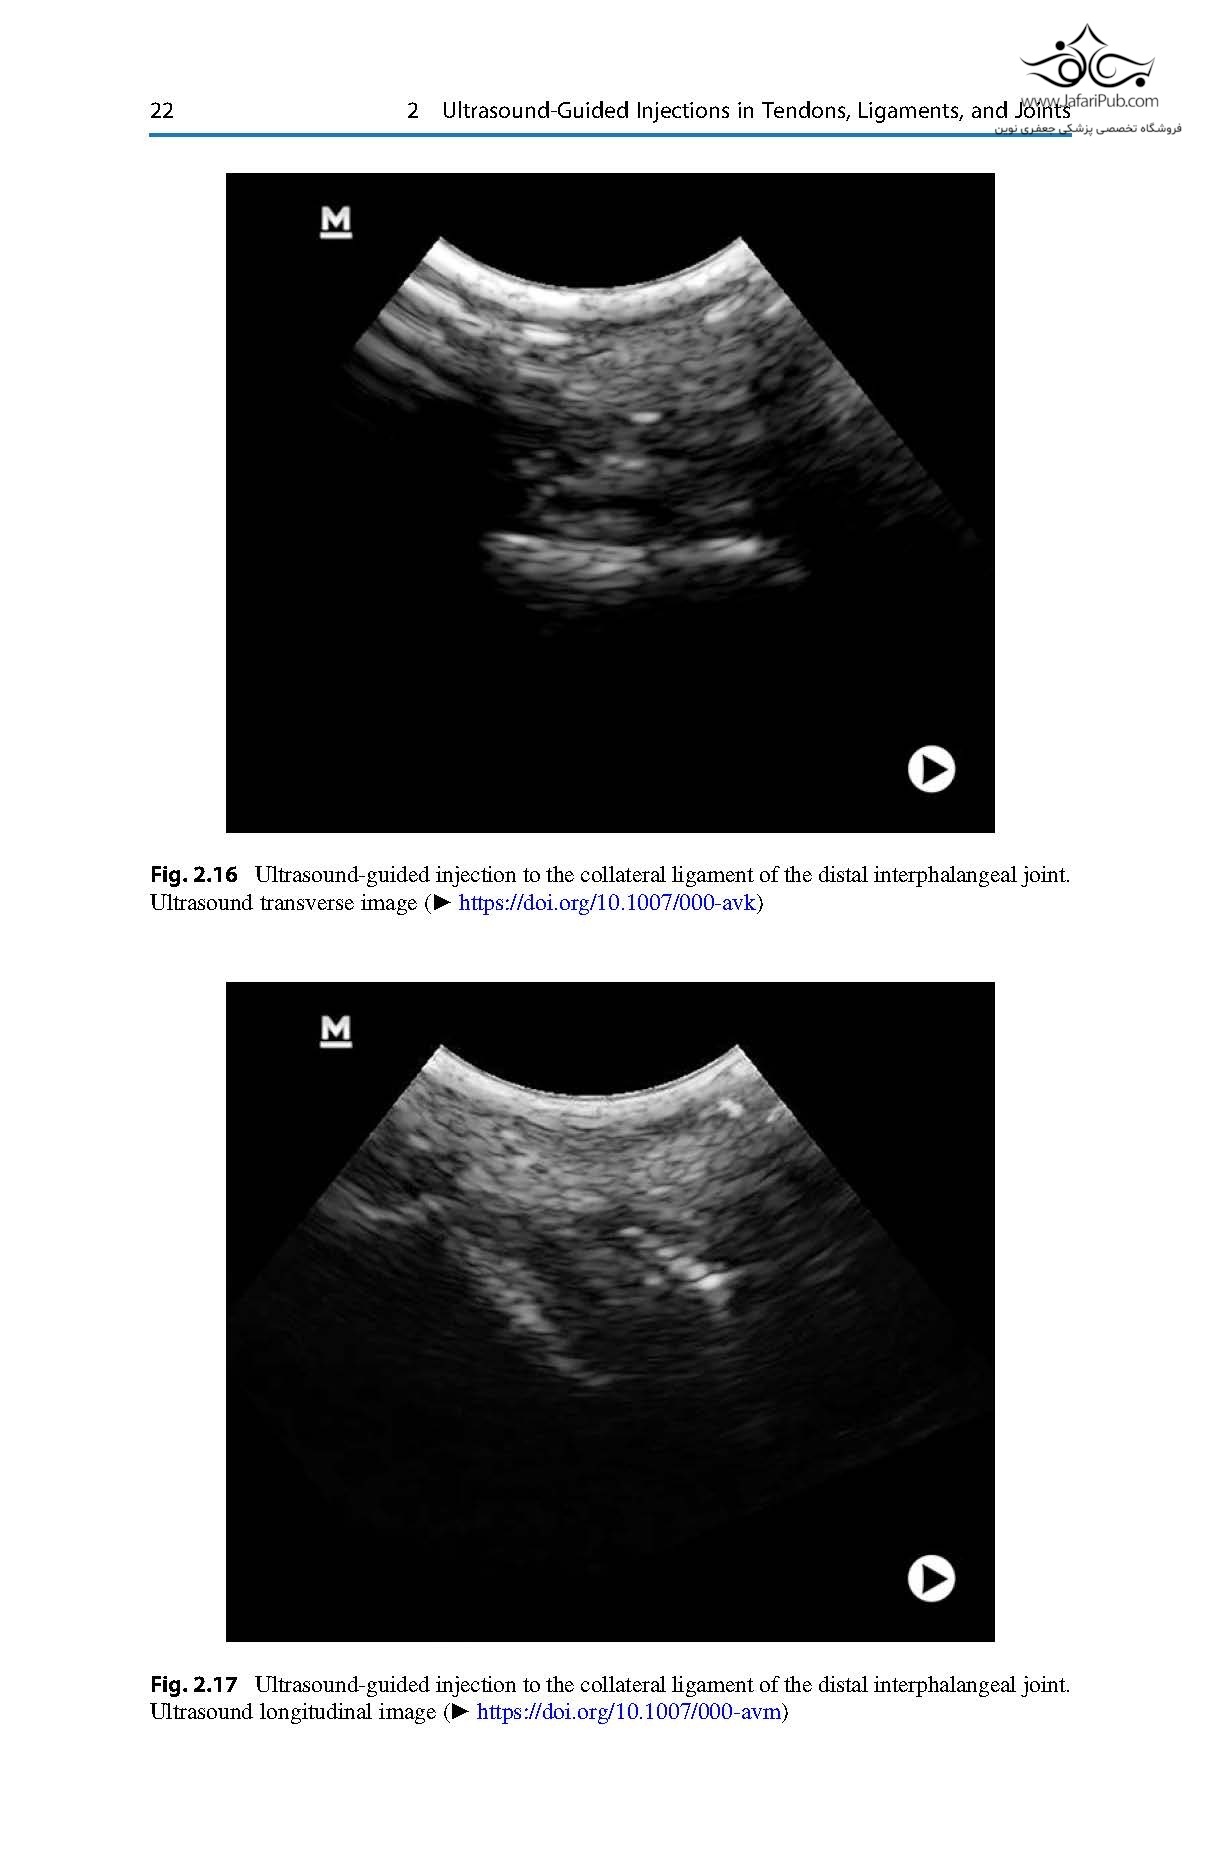

This book serves as a practical guide for equine veterinarians in orthopedics and surgery. It reviews and summarizes the current scientific evidence of the most commonly performed ultrasound-guided procedures for ultrasound-assisted surgery and injections.

For the first time, different techniques are compiled and richly illustrated with pictures and videos to guide the practitioner step-by-step. An initial discussion about the general principles of ultrasound-guided procedures sets the bases for clinicians to understand the general technique and apply it to each approach. Additional chapters describe the most common ultrasound-guided injections in different anatomical structures as well as the surgical approaches that are aided or guided with ultrasound.